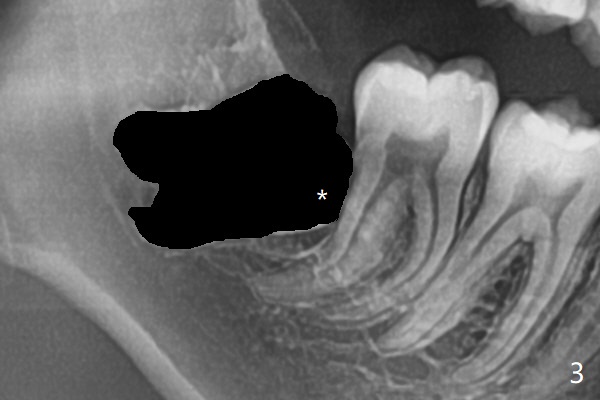

A 19-year-old man returns for #1,16,17 and 32 extraction (Fig.1,2). Because of horizontal impaction of #32 and no bone #31 distal post extraction (Fig.3 *), 3D bond (.5 cc) will be placed in the mesial socket of #32 (Fig.4 red), while Osteogen plug (1/2 (O)) in the distal one. Since there is no bony defect between #17 and 18 after extraction (Fig.5 *), a piece of Osteogen plug (cut half apical) will be inserted in #17 socket, whereas 2 small pieces of Osteogen plug placed in the apical portions (triangle and spindle shaped). Take posterior panoramic X-ray postop (bitewing type, CT format, not XV). There appears bone formation in the socket 5 months postop (Fig.10,11).

Since #32 sockets seem large, extending mesiobuccal (Fig.6), Bond Apatite (1 cc) is placed instead (Fig.7 B), covered by 1/3 of Osteogen plug (O) and sutured with 4-0 PGA. Extraction of #17 is also difficult. As 2 sockets are indistinct, a piece of Osteogen plug with split is placed (Fig.8) upside down (Fig.9 vs. Fig.5). There appears bone formation in the socket 5 months postop (Fig.10,11).